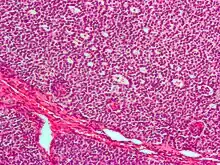

| Micrograph of a granulosa cell tumour, a type of sex-cord–gonadal stromal tumour. H&E stain. | |